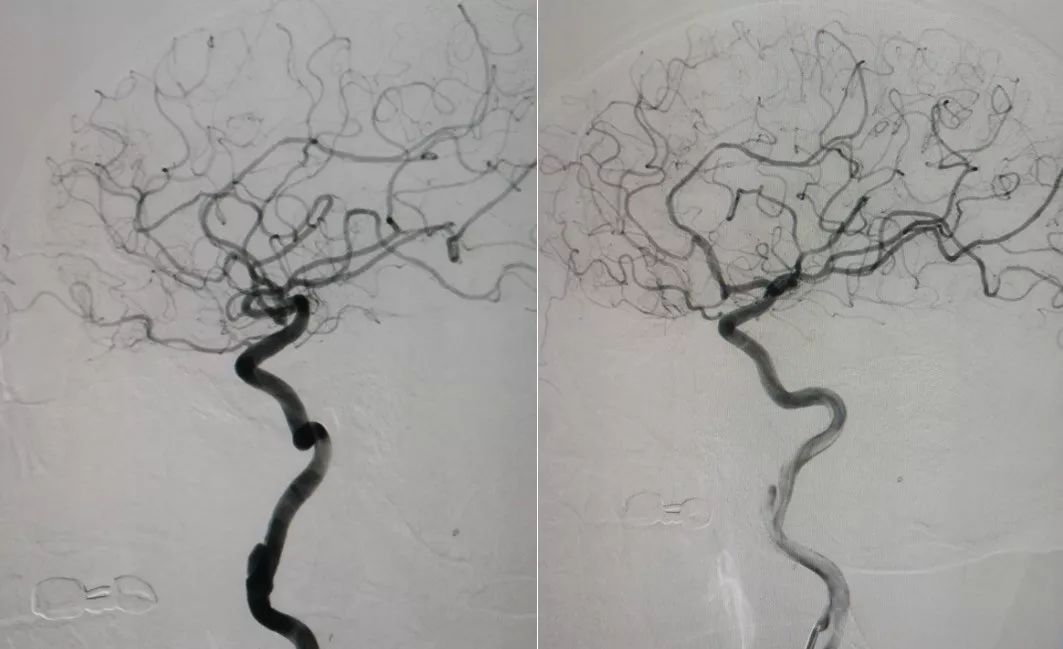

当地医院MRA检查(2019-9-9)(图2)

图2

当地医院MRA检查(2019-9-9)(图3)

图3

1、局麻后右侧股动脉穿刺置入6F动脉鞘,泥鳅导丝导引下6F导管超选至左侧颈内动脉起始段,造影示左侧颈内动脉C1段夹层动脉瘤。因我院机器未安装三维测试,运用圆规和尺子测量,得出血管直径10.5 mm,6F导引导管直径0.45 mm,6F导引导管实际管腔直径2.12 mm,根据公式计算2.12/0.45=X/10.5 X=4.946 mm ;考虑血管实际直径约5.0 mm,因此选择5.5 mm*35 mm Tubridge支架(图4)。

3、术后造影显示Tubridge支架位置良好,动脉晚期瘤内造影剂滞留明显(图6 )。

图6